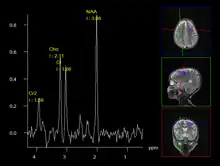

When a lesion is suspected of having CNS metastases and its primary site is unknown, additional imaging and biopsies maybe necessary for an accurate diagnosis.[14] These procedures allow medical practitioners to examine and evaluate the histology, or micro-anatomy, of the suspected tissue.[15]

Biopsies involve surgical removal of the suspected tissue but can be invasive. They warrant a thorough evaluation of their necessity and the patient’s capability to withstand the side effects.

A less intrusive alternative imaging technique is magnetic resonance spectroscopy (MRS), which is used to determine the chemical compositions of cells. However, it is not as reliable as biopsies.[12]